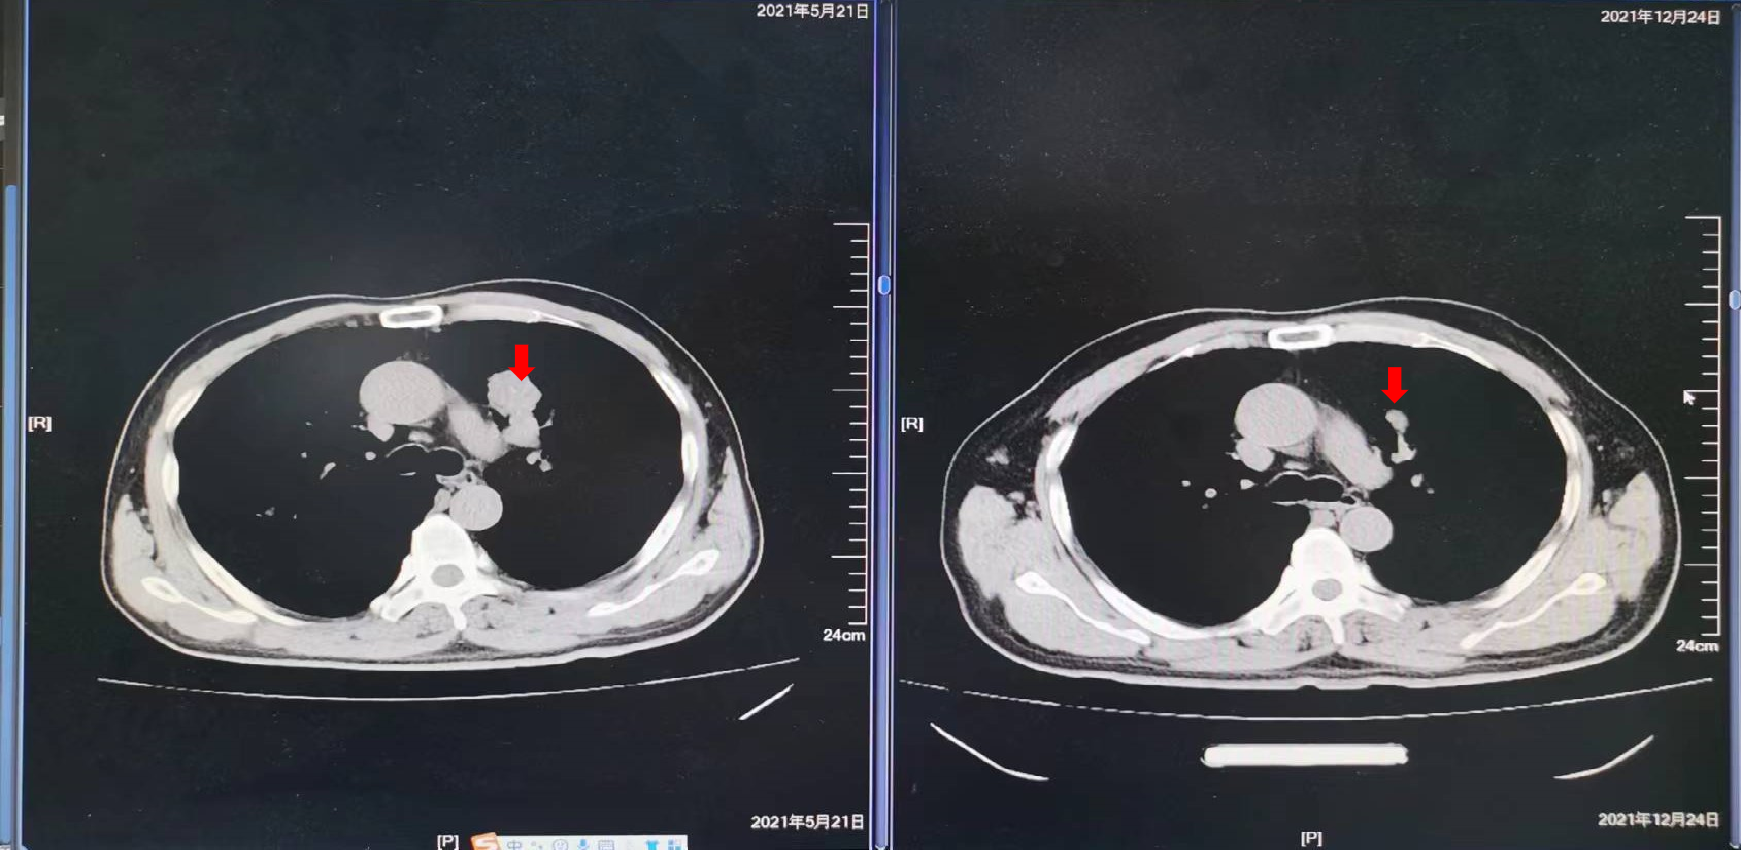

2019年10月16日:复查影像学检查提示新发肺转移,建议贝伐珠单抗,患者拒绝,继续XELOX方案化疗2周期,卡培他滨口服1周期,疗效为PD。

2021年5月27日:开始口服曲氟尿苷替匹嘧啶片(TAS-102)55mg每日2次 d1-5,d8-12,Q4W配合信迪利单抗免疫治疗。

疗效评价:SD,患者右腹股沟肿胀疼痛明显减轻,停用止痛药,PFS时间为10个月,主要不良反应为Ⅱ度骨髓抑制。